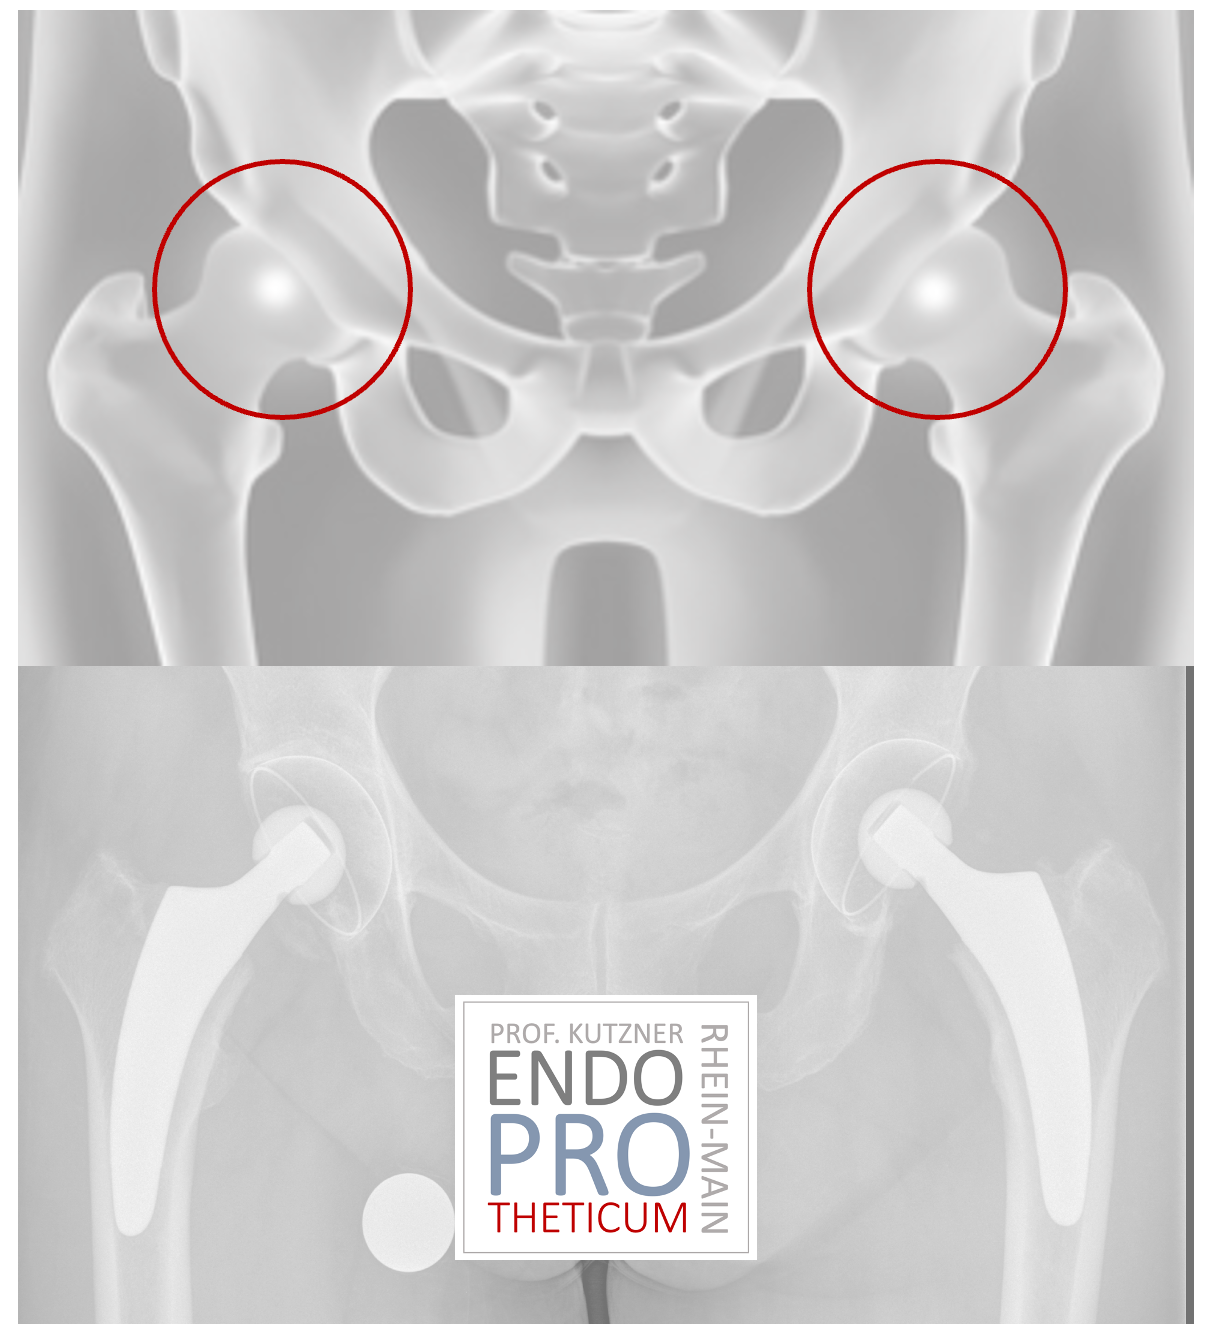

Short-stem prostheses have become increasingly popular in recent years. The implantation of a short-stem PROSTHESIS aims to preserve the bone and create favorable conditions for revision without changing the basic concepts of conventional hip arthroplasty.

SHORT-STEM PROSTHESES were developed decades ago to ensure a bone- and soft-tissue-sparing implantation approach; in recent years, numerous innovations and modifications have come onto the market.

The concept of modern calcar-guided short stems in hip arthroplasty aims at the precise reconstruction of the individual, anatomical hip geometry. A bone and soft tissue-sparing implantation technique is used in conjunction with a physiological load in the part of the femur near the joint in order to preserve the bone in the long term.